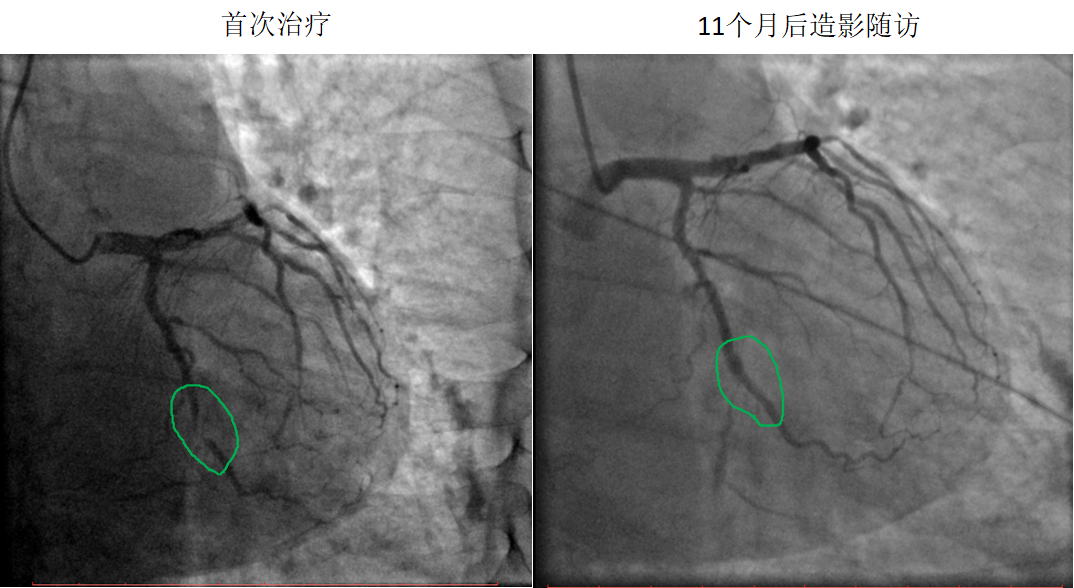

藥物球囊治療閉塞病變

患者:男,51歲

病變部位:LCX中段OM處100%閉塞

使用藥物球囊:2.0 x 20 mm

11個月后造影

隨訪:LCX中段OM發(fā)出處通暢